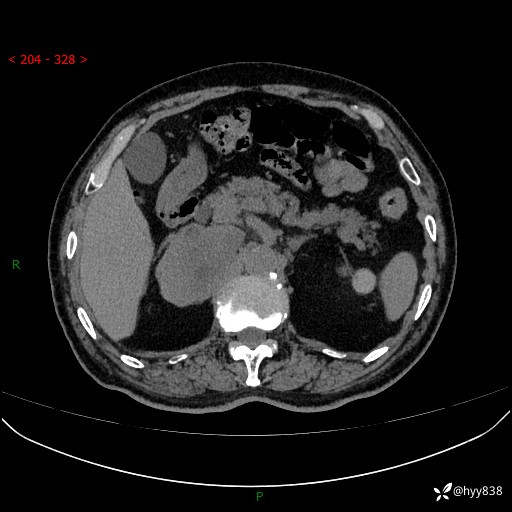

【患者信息】:76岁/男

【主诉】:检查发现右侧肾上腺占位6天

【现病史及既往史】:患者6天前体检发现右侧肾上腺占位,无腰痛,无放射痛,无尿频、尿急、尿痛及肉眼血尿,无畏寒、发热,无恶心、呕吐,今为求进一步治疗,遂来我院就诊,门诊拟“右侧肾上腺占位”收住入院。 起病以来,患者精神、饮食、睡眠可,大小便如常,体力体重无明显变化。

【检查】:肾上腺CT平扫+增强